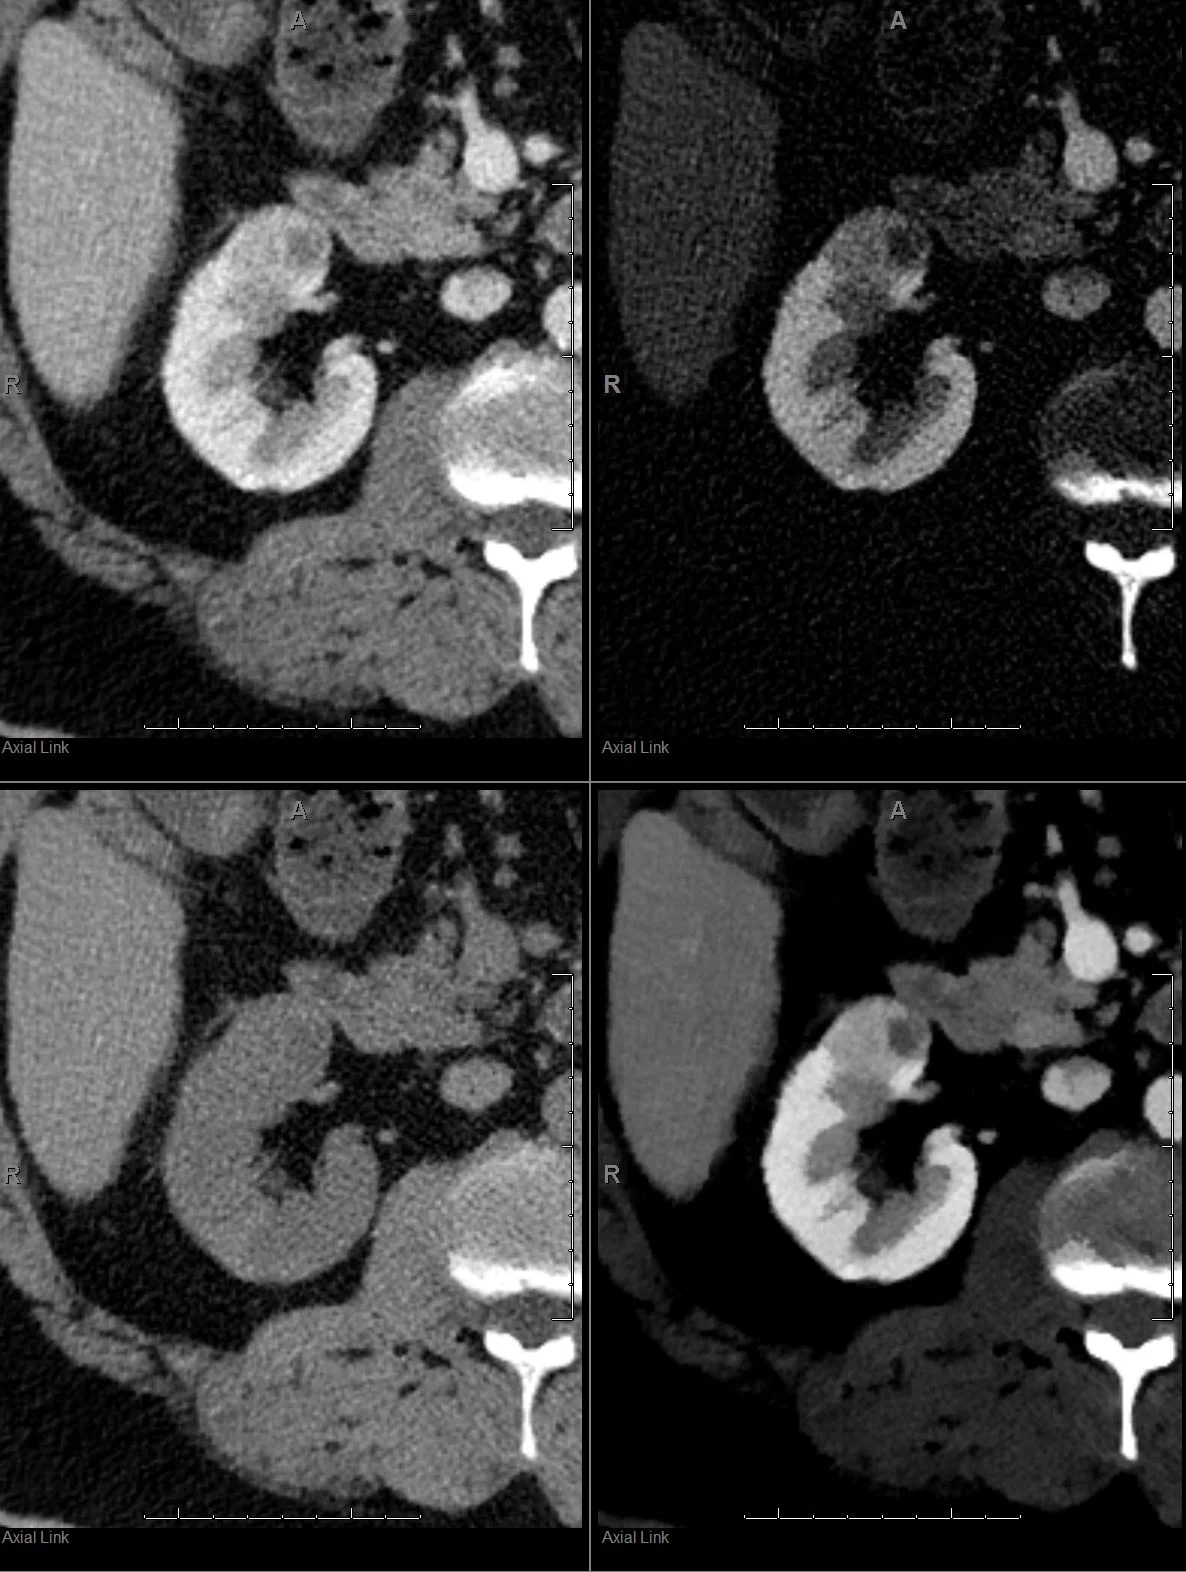

Screenshot from PACS (clockwise from top left): Conventional CT, iodine map, 40 keV mono-energy image and virtual non-contrast. The lesion is a renal cell carcinoma, and all you need is one glance at the spectral recons! At Hennepin, all these recon…

Screenshot from PACS (clockwise from top left): Conventional CT, iodine map, 40 keV mono-energy image and virtual non-contrast. The lesion is a renal cell carcinoma, and all you need is one glance at the spectral recons! At Hennepin, all these recons are automatically generated by scanner and exported to PACS.

In this case, there is obvious iodine uptake in the kidney lesion, and the lesion shows >90 HU enhancement relative to the virtual non-contrast. All this can be done on PACS itself, without needing any fancy processing. The PACS screenshot below illustrates the point.